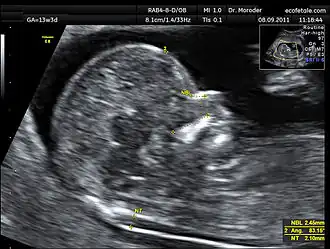

![]() Measurements of fetal nuchal translucency, nasal bone and facial angle according to the standards of the Fetal Medicine Foundation | |

A nuchal scan or nuchal translucency (NT) scan/procedure is a sonographic prenatal screening scan (ultrasound) to detect chromosomal abnormalities in a fetus, though altered extracellular matrix composition and limited lymphatic drainage can also be detected.[1]

Procedure

Nuchal scan (NT procedure) is performed between 11 and 14 weeks of gestation, because the accuracy is best in this period. The scan is obtained with the fetus in sagittal section and a neutral position of the fetal head (neither hyperflexed nor extended, either of which can influence the nuchal translucency thickness). The fetal image is enlarged to fill 75% of the screen, and the maximum thickness is measured, from leading edge to leading edge. It is important to distinguish the nuchal lucency from the underlying amniotic membrane.[9]

Normal thickness depends on the crown-rump length (CRL) of the fetus. Among those fetuses whose nuchal translucency exceeds the normal values, there is a relatively high risk of significant abnormality.

How to define a normal or abnormal nuchal translucency measurement can be difficult. The use of a single millimeter cutoff (such as 2.5 or 3.0 mm) is inappropriate because nuchal translucency measurements normally increases with gestational age (by approximately 15% to 20% per gestational week from 10 to 13 weeks).[10] At 12 weeks of gestational age, an "average" nuchal thickness of 2.18mm has been observed; however, up to 13% of chromosomally normal fetuses present with a nuchal translucency of greater than 2.5mm. Thus for even greater accuracy of predicting risks, the outcome of the nuchal scan may be combined with the results of simultaneous maternal blood tests. In pregnancies affected by Down syndrome there is a tendency for the levels of human chorionic gonadotropin (hCG) to be increased and pregnancy-associated plasma protein A (PAPP-A) to be decreased.